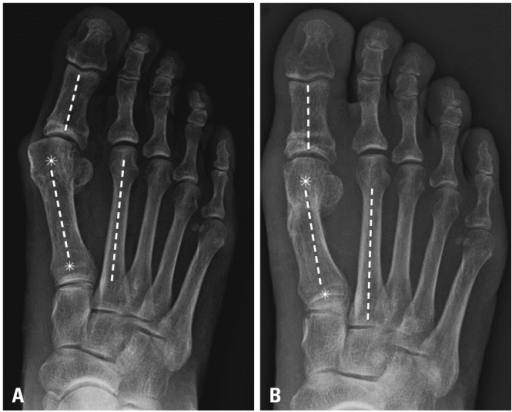

Clinical image for Hallux Valgus

What radiographic angles should be measured on this weight-bearing AP foot radiograph, and what are the normal values?